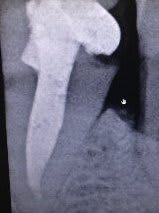

Je fais appel à vos idées ;je me trouve face à une 36 que je viens de dévitalisée car trés délabrée et cette dent présente une racine unique avec une chambre pulpaire super large ,je vais essayer de vous mettre la radio ;

probléme je ne pense pas que mes forets de chez APOL soit en diametre suffisant pour trouver un contcat sur les parois dentinaires et je n'aimerais pas que mon ancrage soit scéllé dans de la gutta seulement